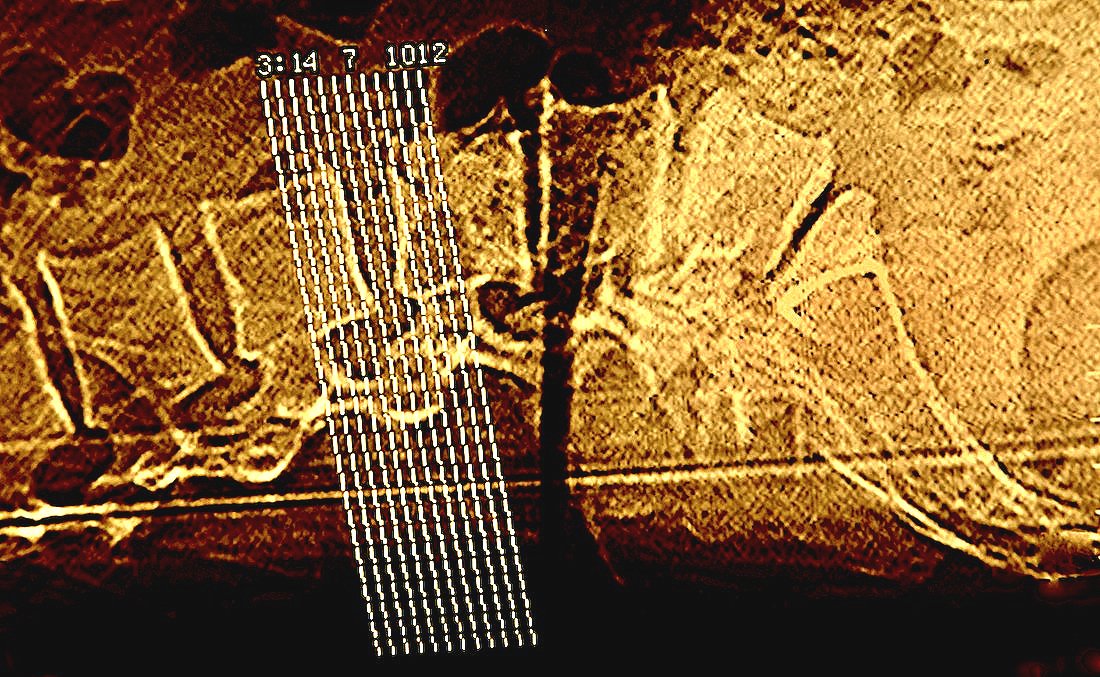

saturday night fever (girl meets boy diptych)

Selected for July/Aug 2022 exhibition in Art No.23’s Barcelona gallery.